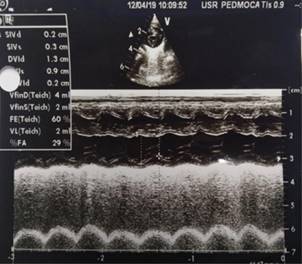

Por ecocardiograma, se descarta participación cardiológica (Figura 2), por lo que, aunado a acidosis metabólica, hiperlactatemia e índice de oxigenación de 15, se estable el diagnóstico de SDRA neonatal.

Figura 2: Ecocardiograma. Se evidencia buena función sistodiastólica ventricular izquierda, con gasto cardiaco de 250 mL/kg/minuto, sin hallazgos secundarios de hipertensión pulmonar. Ductus arterioso cerrado.